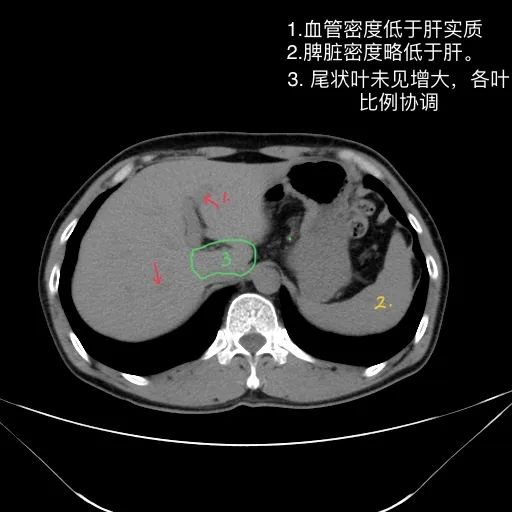

肝脏缩小,包膜凹凸不平,肝裂增宽,各叶比例失衡,肝实质密度不均,肝S4小片低密度影,约cm;胆囊不大,其内未见异常密度影,胆道系统未见扩张;胰腺、脾脏形态、密度、大小未见异常;双肾上腺及双肾形态、密度、大小未见异常,双输尿管未见扩张,膀胱充盈良好,壁光滑,其内未见异常密度影;前列腺未见异常;胃肠道未见充盈,壁未见明确增厚,食管胃底多发迂曲、增粗血管,腹部及腹膜后未见肿大淋巴结;腹水。

1.肝硬化失代偿表现(腹水,食管胃底静脉曲张)。

2.肝S4小片低密度影,建议复查或进一步检查。